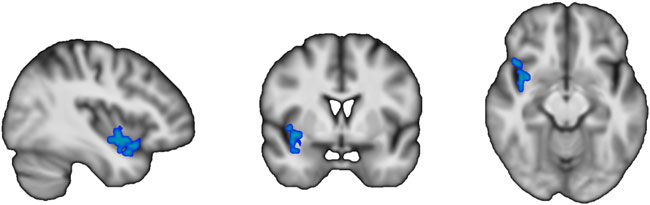

| プラセボと比較して、アロニアメラノカルパ抽出物は全脳および灰白質の脳血流量に影響を与えず、皮質および皮質下脳領域の脳血流量にも変化は見られなかった(表3および図S2)。ボクセル単位の解析では、アロニアメラノカルパ抽出物補給後にプラセボと比較して1つのクラスターで局所脳血流が有意に低下したことが観察された(表3)。このクラスターの体積は992 mm 3(124ボクセル)で、脳血流は4.4 ± 3.6 mL/100 g脳組織/分減少した(ピークMNI座標:X = 29、Y = 29.7、Z = 64、p = 0.004)。ハーバード・オックスフォード・アトラスに基づくと、平均的な位置の確率は、右島皮質(30.8%)、側頭葉(9.8%)、前頭眼窩皮質(4.0%)、および平面極(1.8%)でした(図1を参照)。 |

図1. 高齢者における3次元モントリオール神経研究所(MNI)テンプレートで取得したすべての脳血流データを含むボクセル単位の比較結果。 アロニアメラノカルパ抽出物投与後、プラセボ投与群と比較して1つのクラスターで脳血流が減少した(家族別誤差補正済み、n = 26)。このクラスターの体積は992 mm 3(124ボクセル)で、脳血流は4.1 ± 3.5 mg/100 g brain tissue/min減少した(ピークMNI座標:X = 29、Y = 29.7、Z = 64、P = 0.004)。ハーバード・オックスフォード・アトラスに基づくと、平均位置確率は右島皮質(30.8 %)、側頭葉(9.8 %)、前頭眼窩皮質(4.0 %)、および平面極(1.8 %)であった。 |